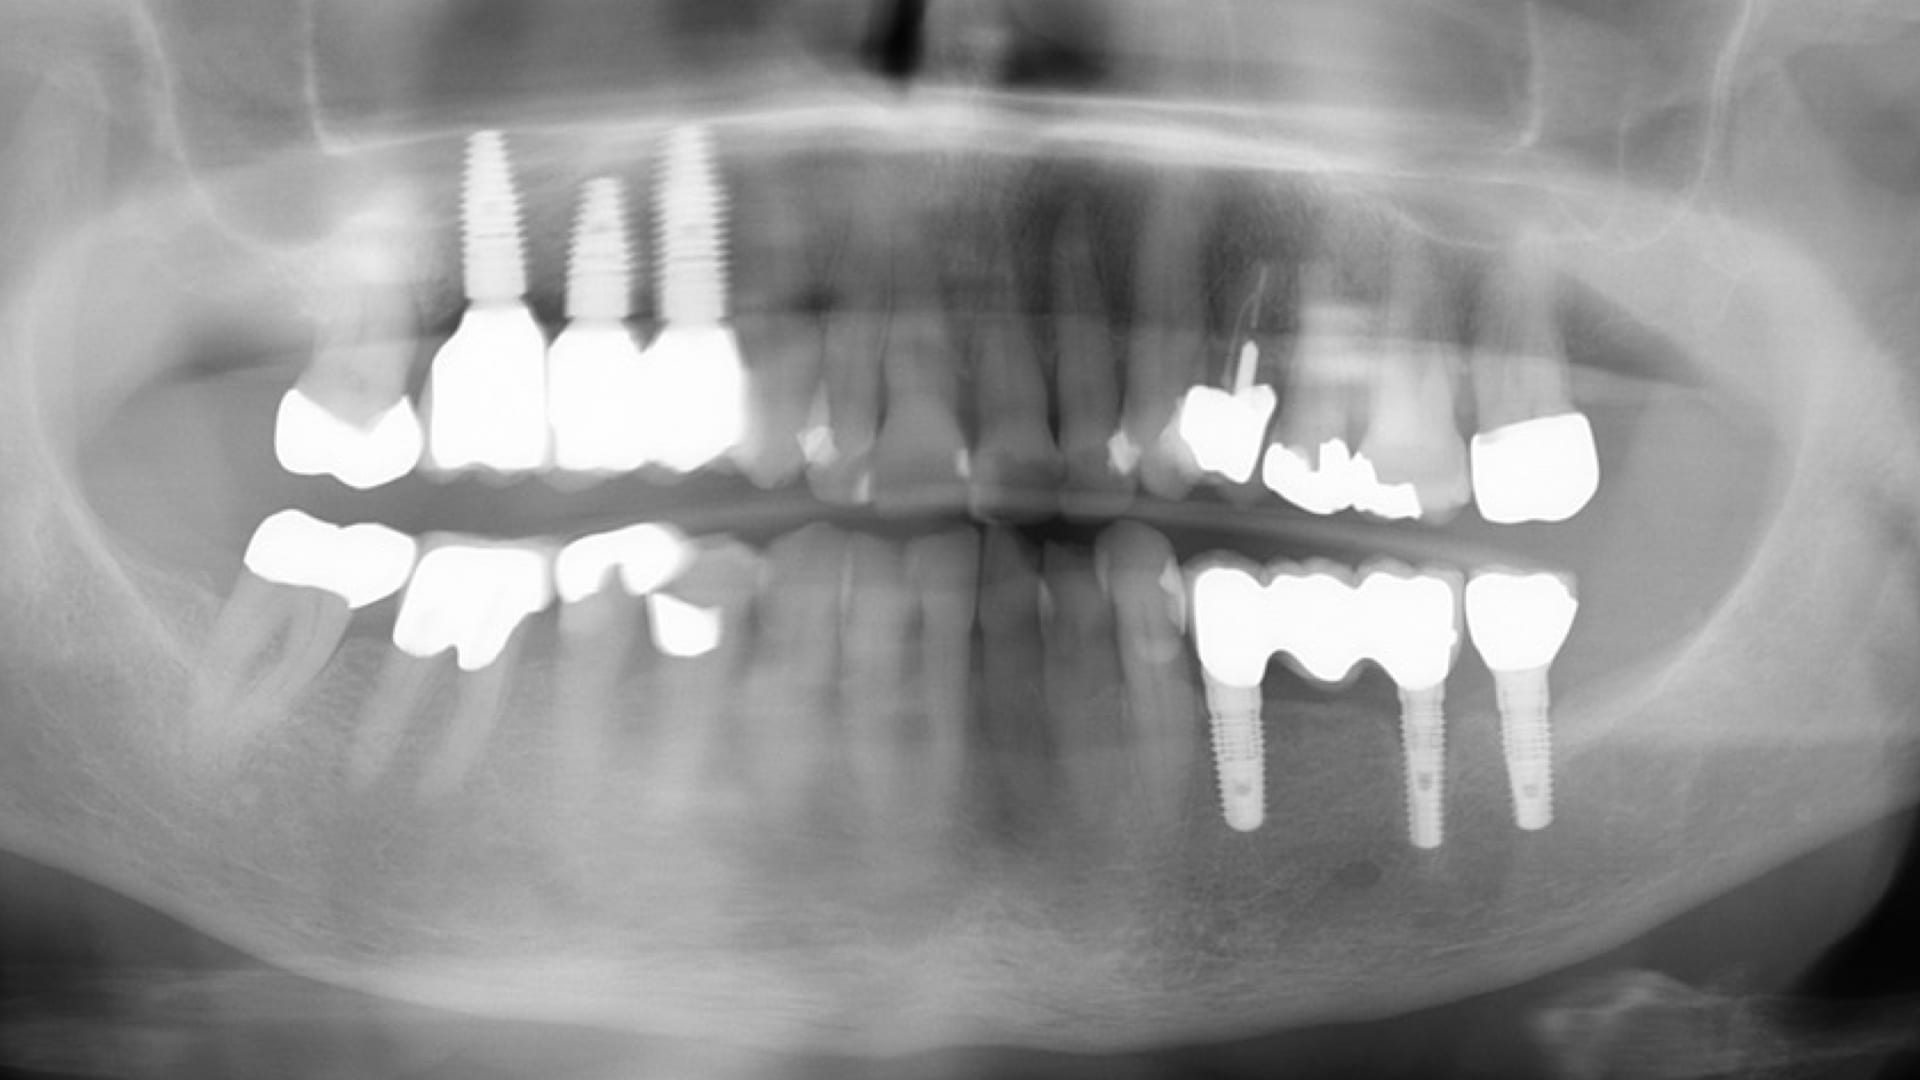

Abb. 20: Abschluß-OPG

Die erstellten digitalen STL-Daten der Modelle wurden in der CAM-Software des 3D-Druckers positioniert und zum Drucker gesendet. In der CAM-Software der Fräsmaschine erfolgte das Nesting der designten Abutments und Verblendkappen in einem Zirkonoxid-Block (Abb. 10 bis 12). Hier endete die digitale Prozesskette im vorliegenden Fall. Die gedruckten Modelle artikulierte das Dentallabor ein. Ebenso wurden die digitalen Laboranloge im Modell mit Pattern Resin fixiert. Die Aufbereitung der Abutments und die damit verbundene Güte der Oberfläche erfolgte nach dem von Rinke et al. erarbeiteten Protokoll. Zur Verbindung von Variobase und Zirkonoxid kam ein Multilink Hybrid-Abutmen zum Einsatz. Im Anschluss erfolgte die keramische Verblendung der anatomisch reduzierten Zirkonoxid-Kappen nach den Vorgaben des intraoralen Scans (Abb. 13) und der Versand in die Praxis (Abb. 14 und 15). Nach dem Einbringen der Abutments auf Klebebasis mit 35 Ncm (Abb. 16 bis 18) wurden die Schraubenkanäle mit Komposit verschlossen. Die definitiven Kronen wurden nach der Ästhetik-, Funktions- und Okklusionsprüfung mit implantlink semi Forte von Detax eingesetzt (Abb. 19 und 20).